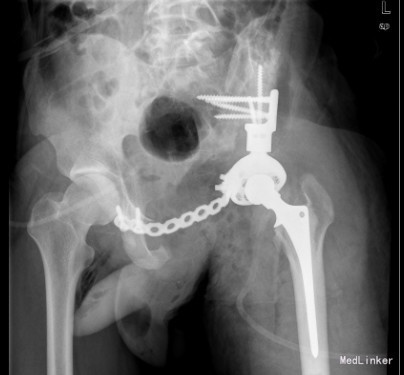

已行左侧骨盆肿瘤切除活检+左半骨盆置换术。由于骨盆区解剖结构复杂,骨盆恶性骨肿瘤的保肢手术极具挑战性。早期文献报导的致死性并发症高达10%,总体并发症更高达75%,5年生存率约为 25%-35%;目前随着技术进步预后相对较好一些。